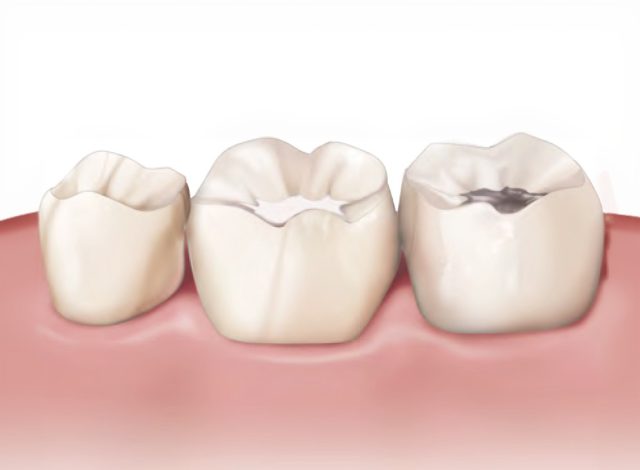

Soins Conservateurs

Préserver votre capital dentaire naturel.

Le meilleur soin est celui qui permet de garder vos dents le plus longtemps possible.

Traitement de caries : Réparer et protéger.

Lorsqu’une carie attaque l’émail, nous retirons la partie abîmée pour stopper l’infection.

Nous reconstruisons ensuite la dent à l’aide d’une résine esthétique (composite) parfaitement adaptée à la couleur de vos dents. Ce soin simple permet de stopper la progression de la carie et de retrouver une dent saine et fonctionnelle.